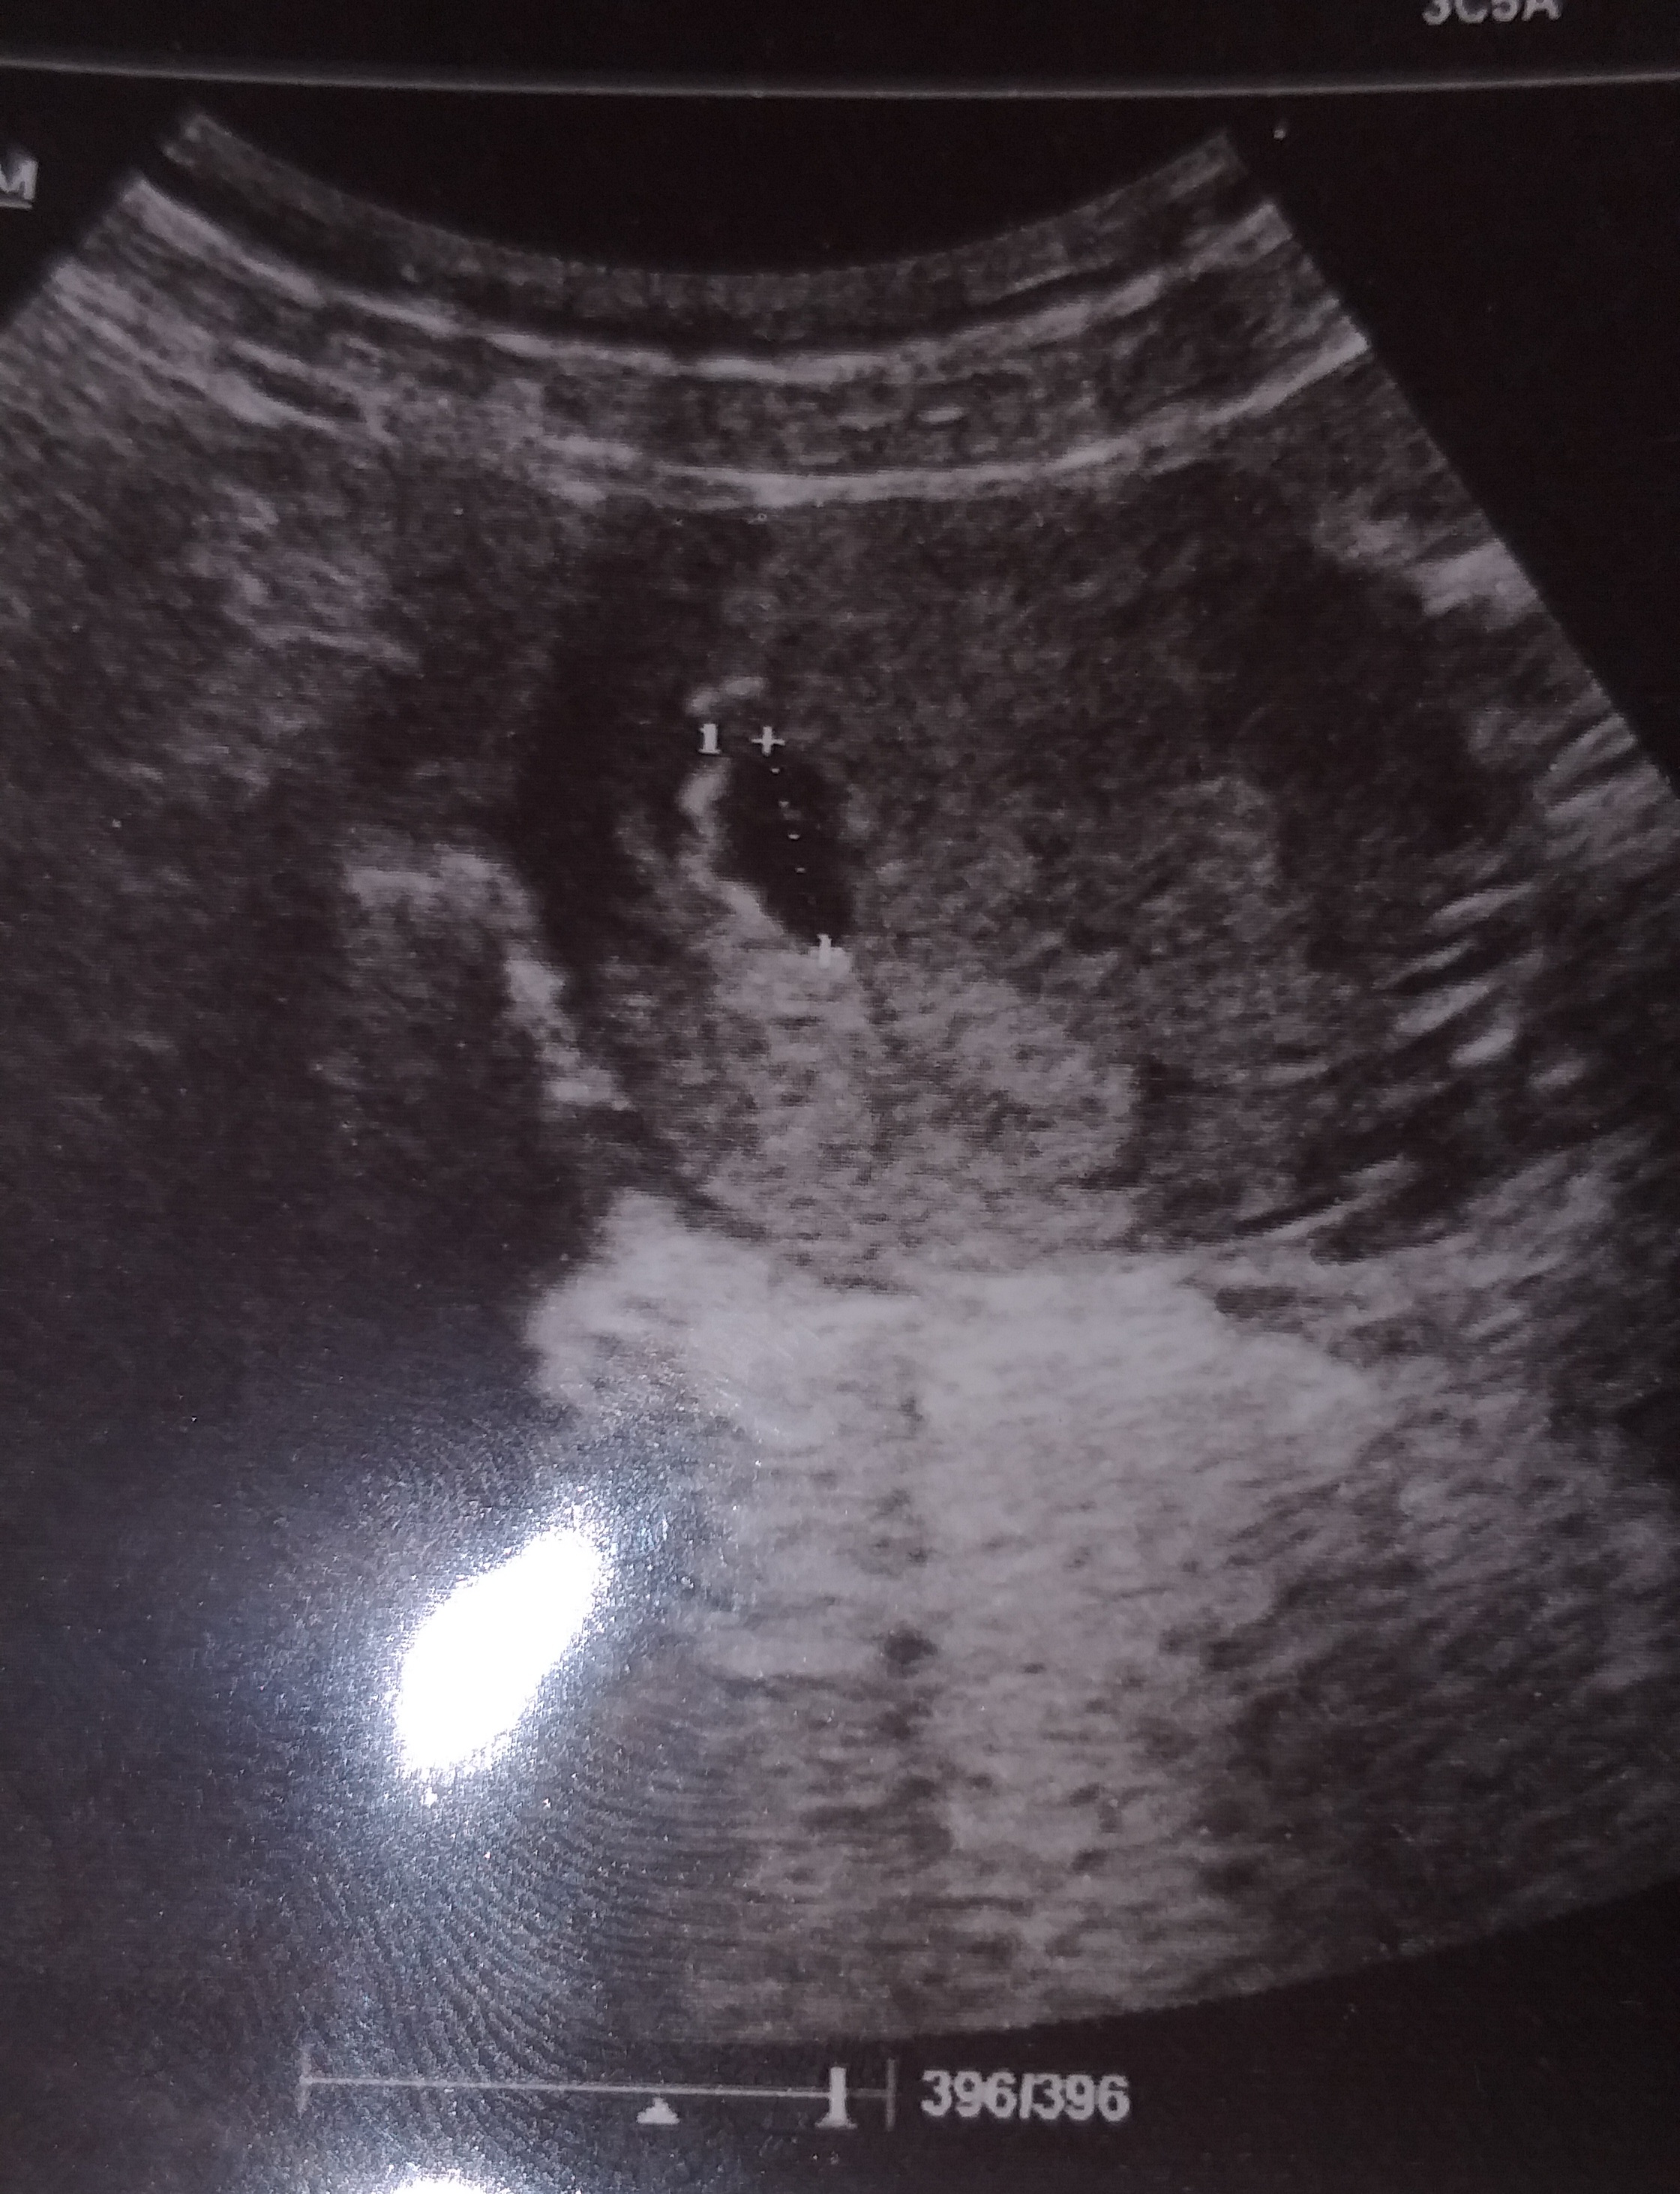

Kızlar günaydın Bu ultrason son kağıdı görümcemin bu sabah biz hastaneye gittik 5 hafta bir günlük şu an yalnız kese etrafında kan olduğunu söyledi doktor açıkçası biz biraz telaşlandık Hani bu şekilde başına gelen ultrason kağıdında bu şekil olan veyahut da doktor söyleyip de Herhangi bir sıkıntı olan varsa Bilgilendirir misiniz

Ekli dosyayı görüntüle 3464